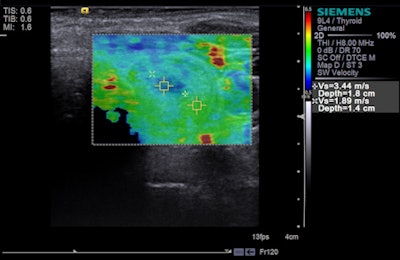

Siemens is also touting several HELX Evolution features: Virtual Touch imaging (VTi), Virtual Touch quantification (VTq), Virtual Touch IQ (VTIQ), and eSie Touch elasticity imaging, designed to visualize and measure tissue stiffness so clinicians can better evaluate anatomy.

Tissue strain analysis of a thyroid lesion using Virtual Touch IQ. Image courtesy of Siemens.VTIQ is based on Siemens' acoustic radiation force impulse (ARFI) technology, and physicians can quantifiably assess the stiffness of tissue in small parts, such as the breast and thyroid. Numerical values are shown simultaneously against a qualitative color map over the user-defined region of interest for greater detail of abnormalities within tissue.

Previously available exclusively on the Acuson S3000 system, VTIQ is now offered on the Acuson S2000 HELX Evolution model as well.

VTi and VTIQ are currently available, whereas VTq is pending FDA clearance.